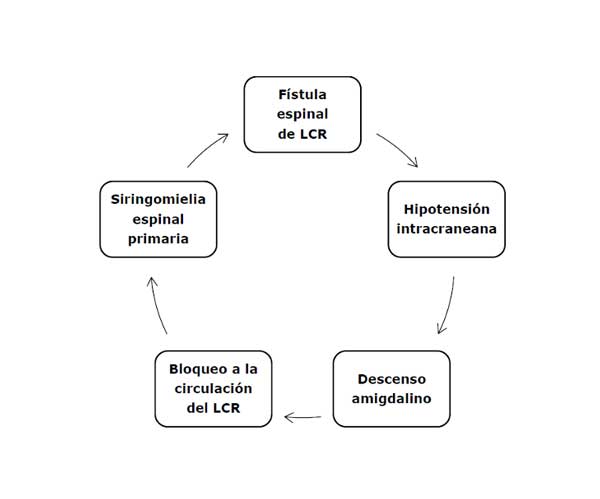

La SM nunca es un evento primario. Generalmente es secundaria a patología ubicada en la fosa posterior o dentro del canal vertebral. El caso aquí descripto indica que la SM fue un “evento terciario” y que la obstrucción a la circulación del LCR fue producida por el descenso amigdalino, al que consideramos como un “evento secundario” ocasionado por la hipotensión intracraneana (HIC), debido al drenaje excesivo de LCR a través de la fístula espinal (Diagrama 1).

Diagrama 1. Cadena de eventos que conducen al desarrollo de la siringomielia.